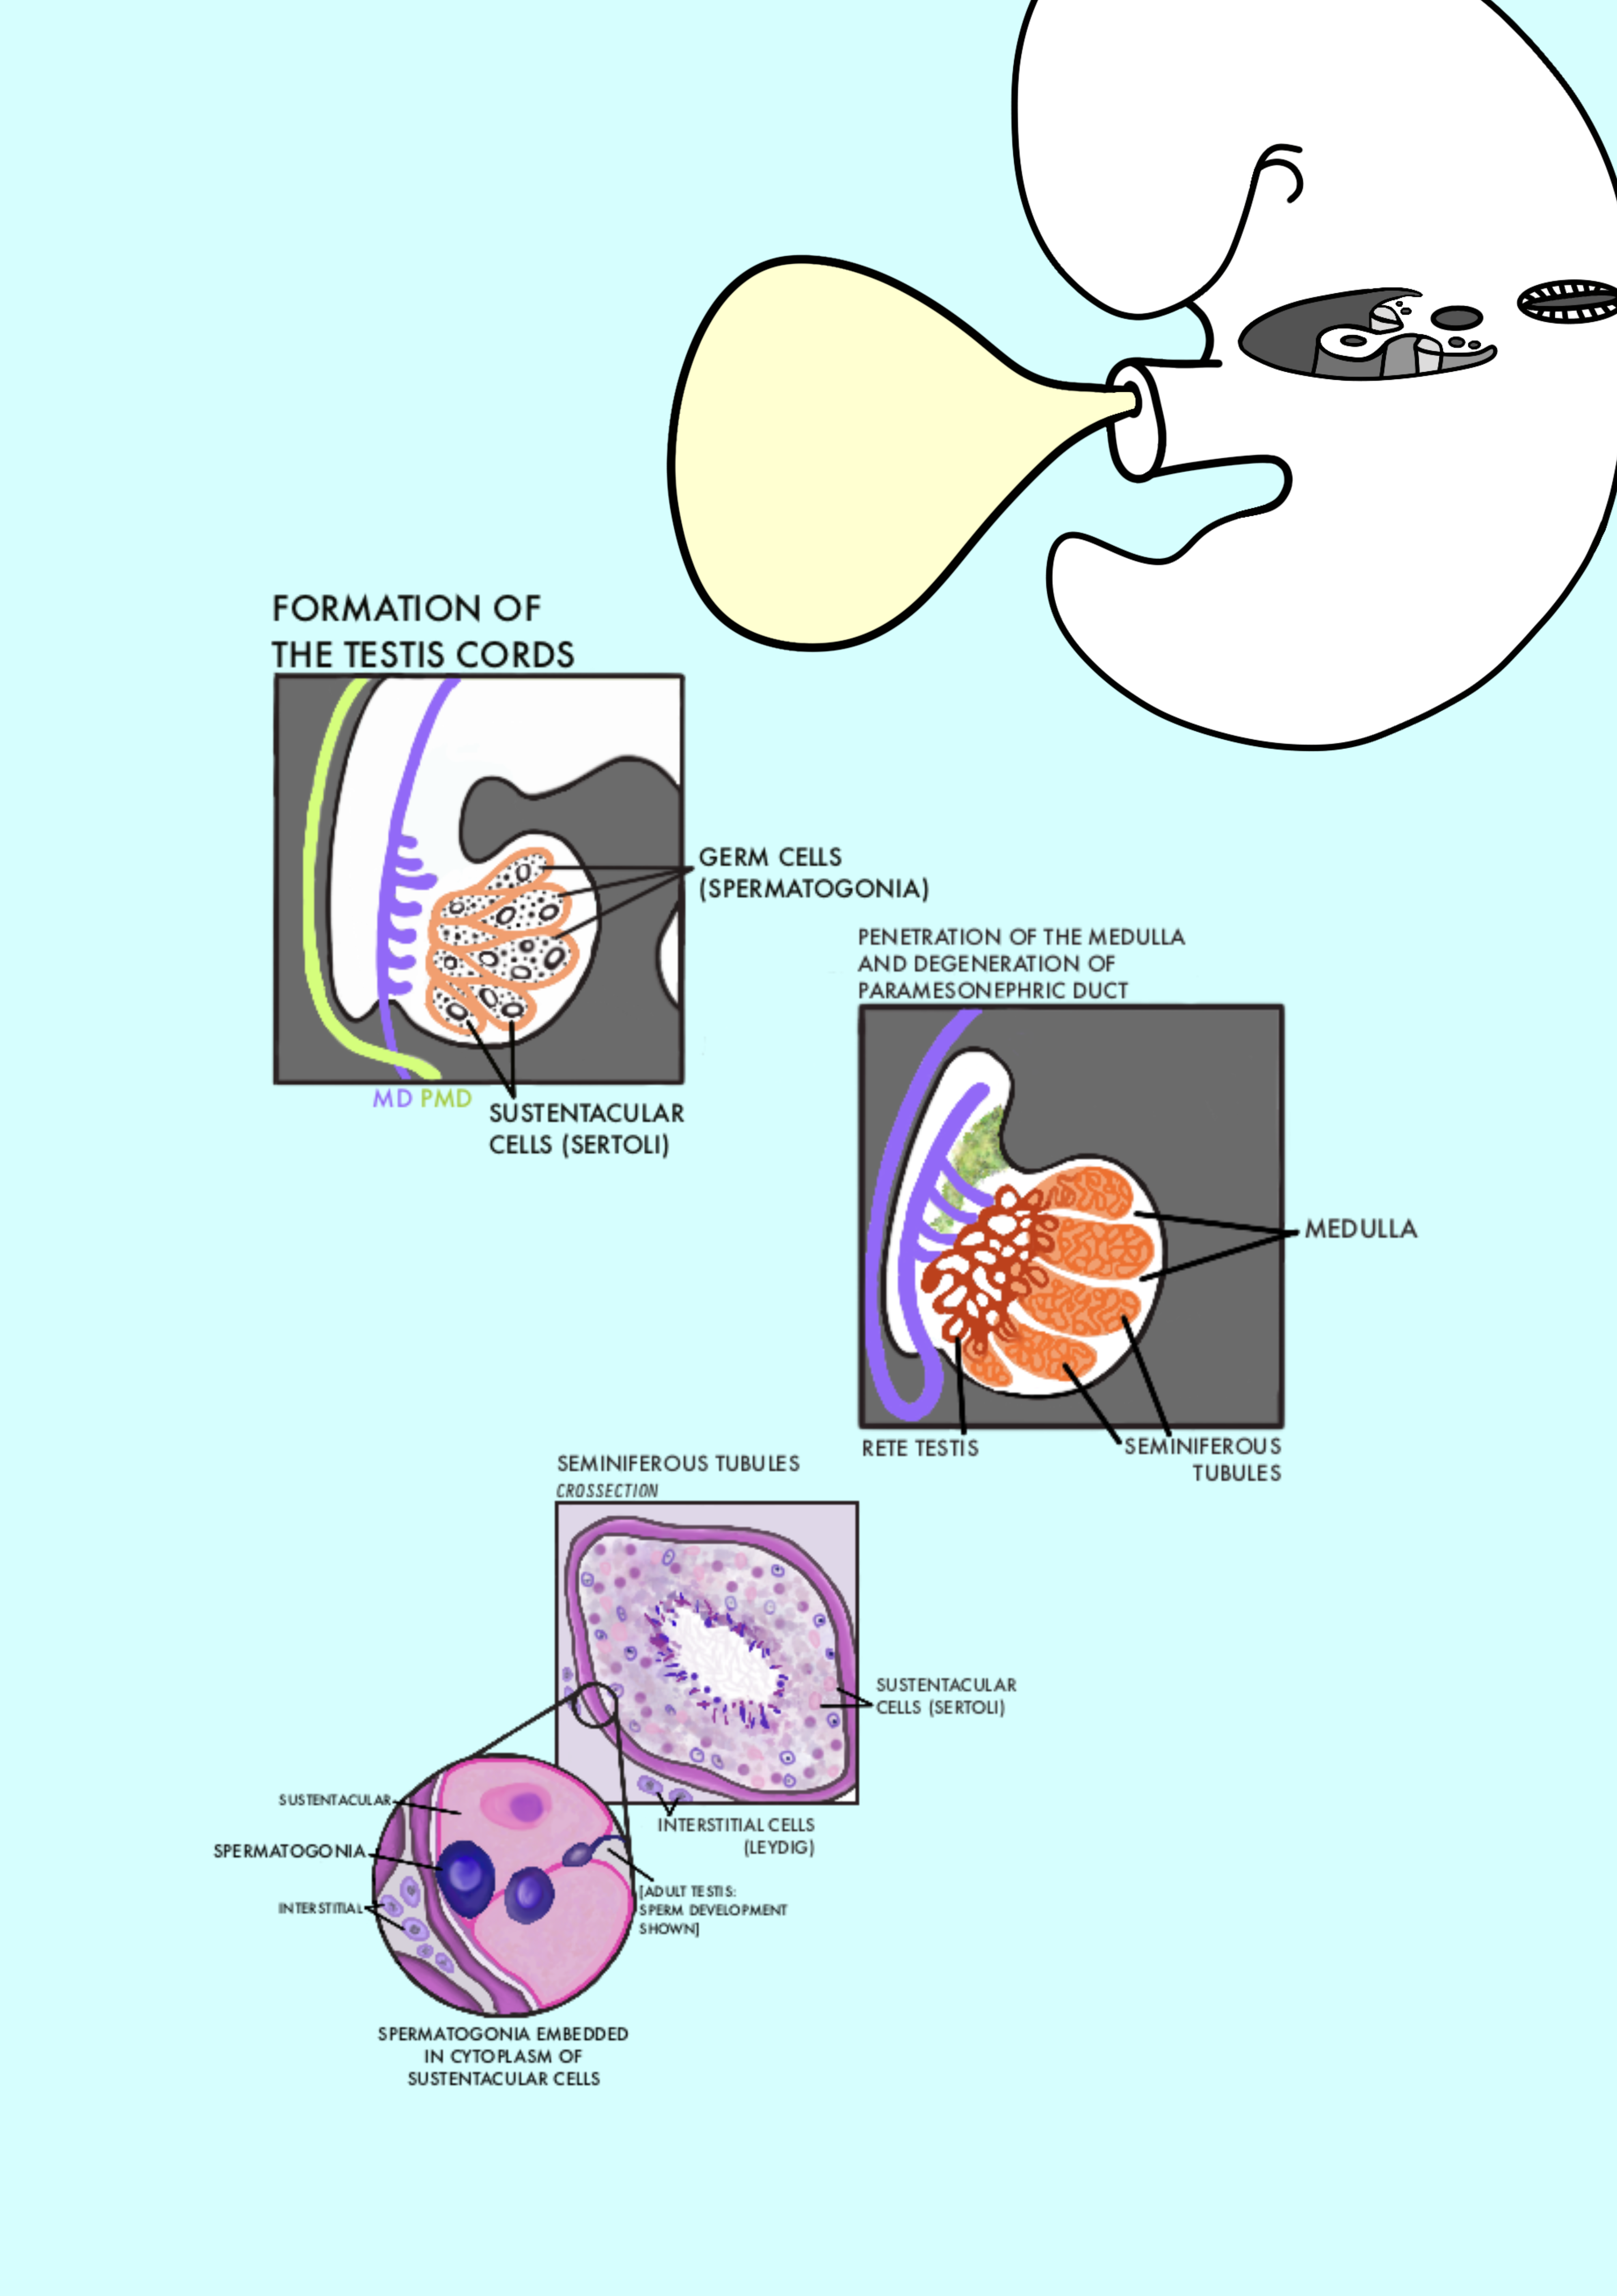

Development of the Genital System